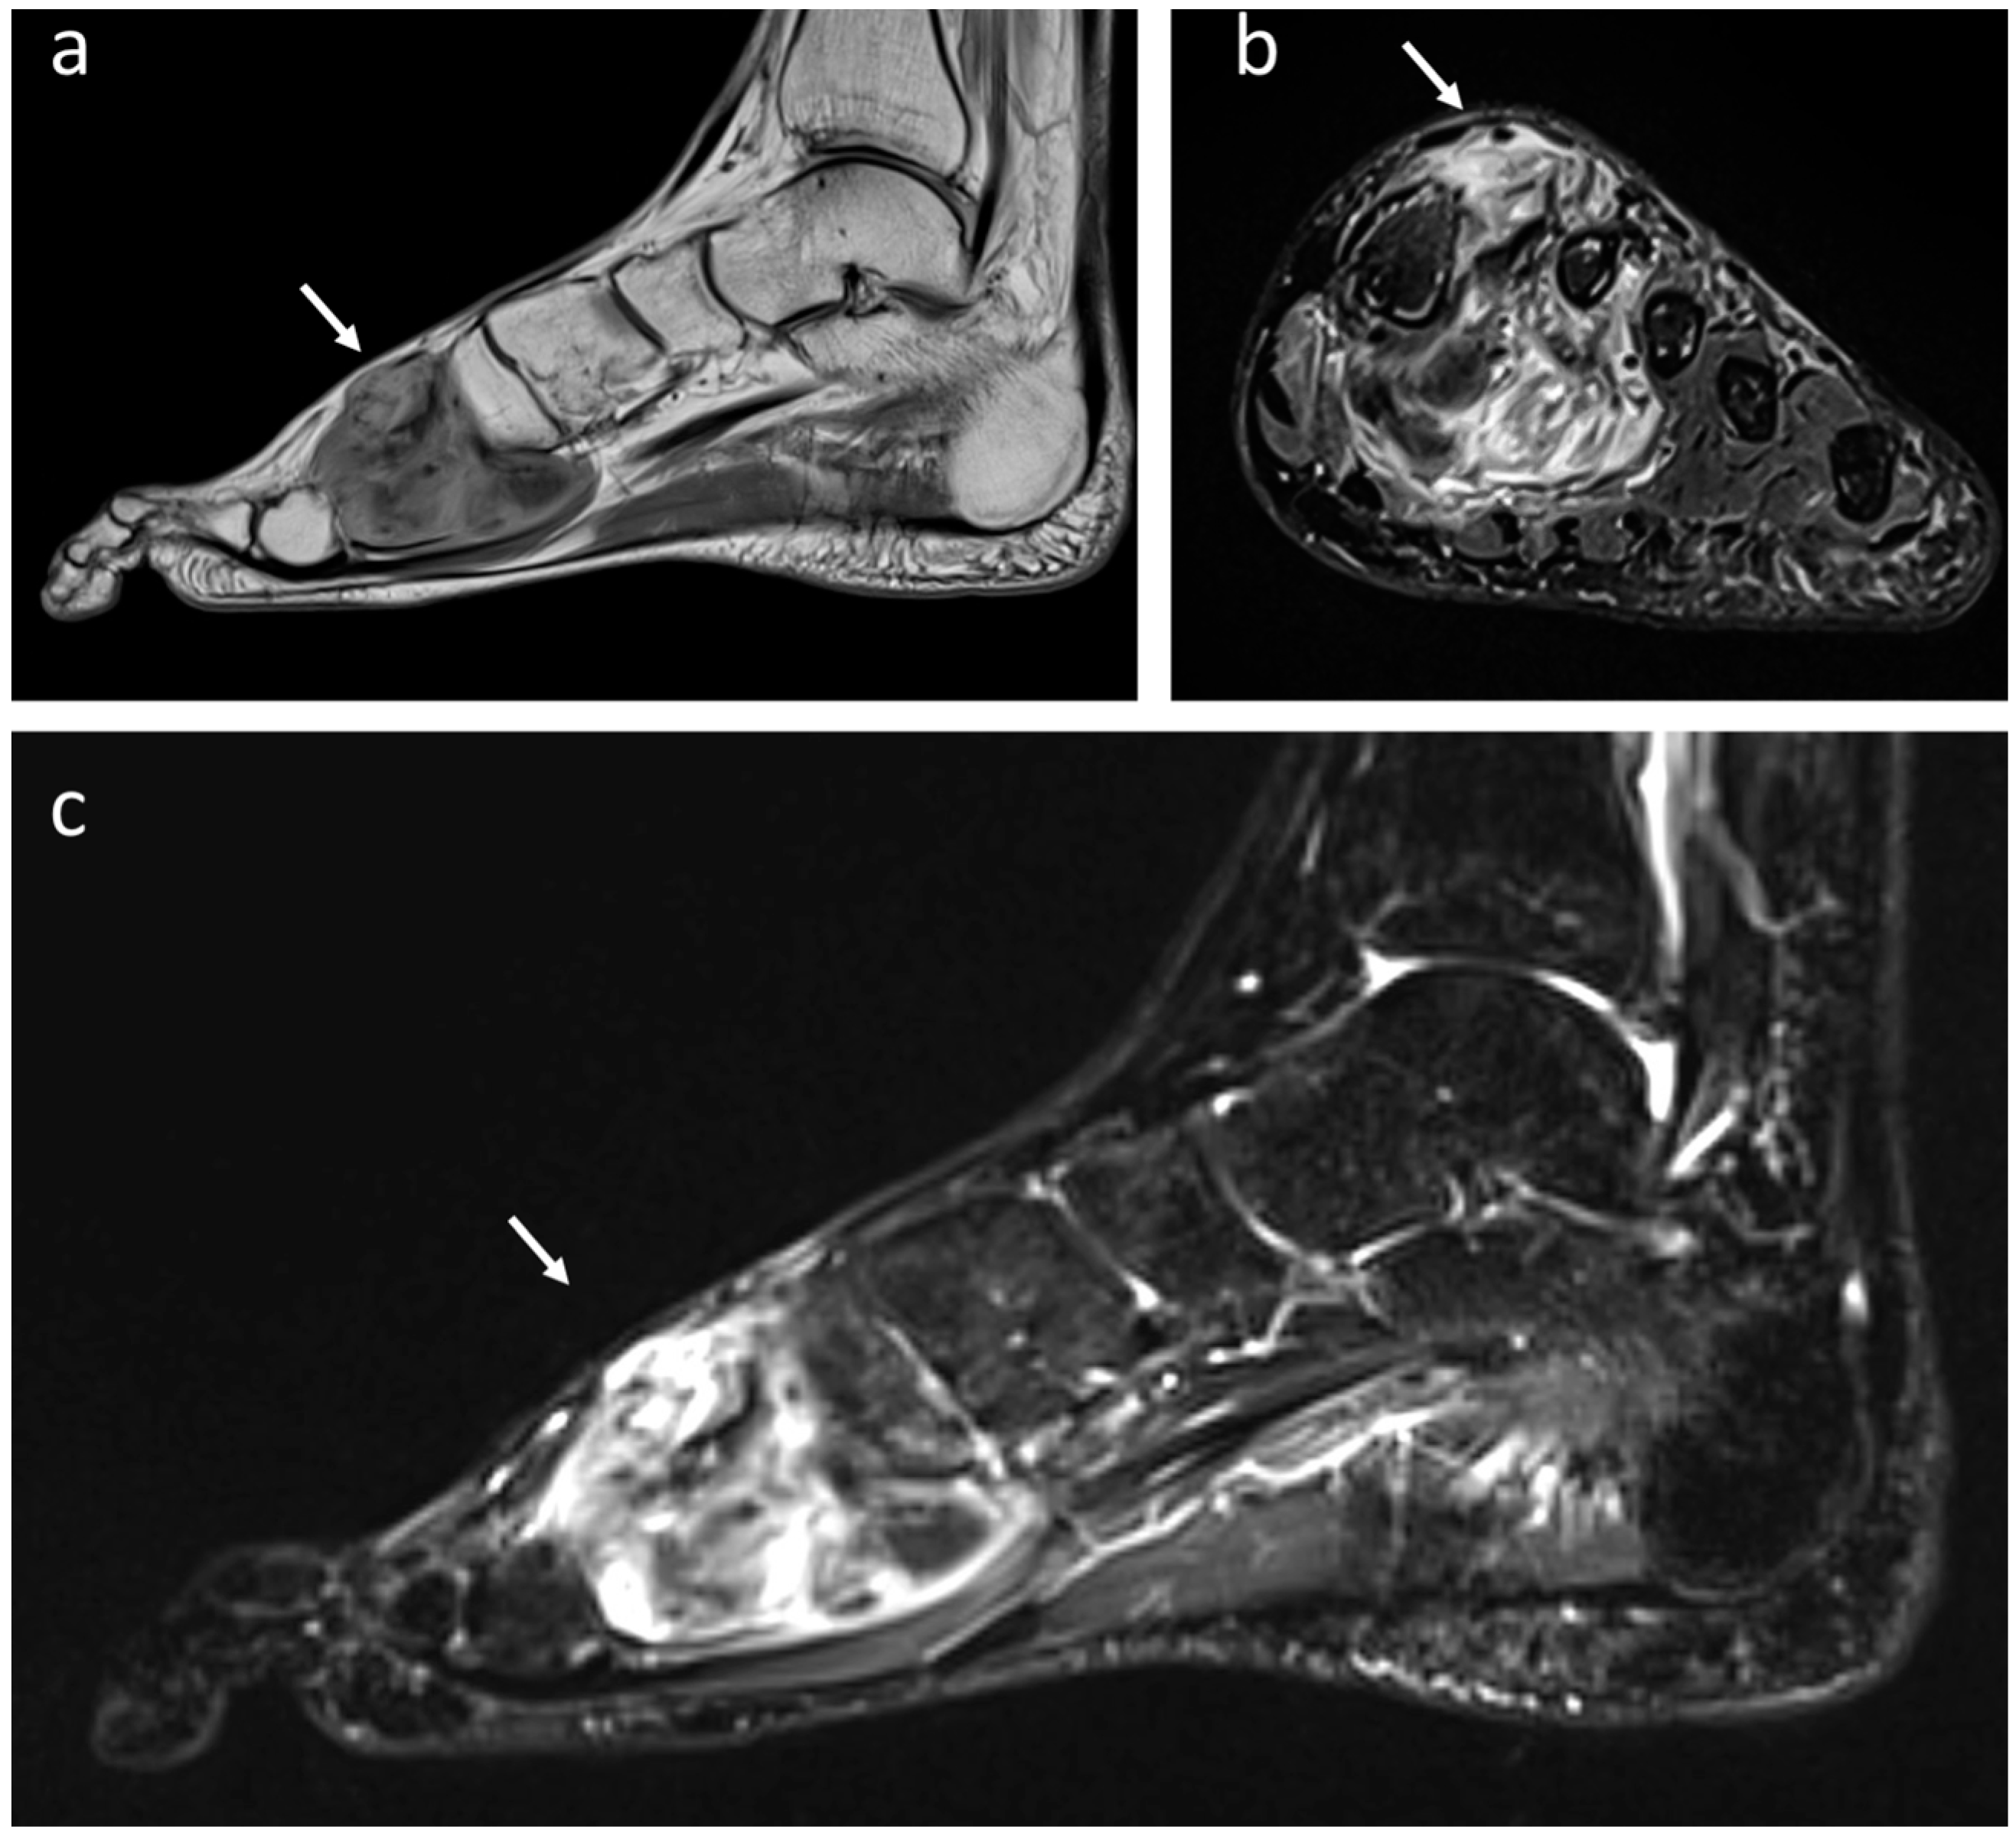

4.7. Liposarcoma